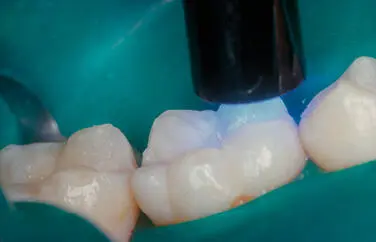

Figura 39Fotoactivación el tiempo indicado por el fabricante del composite - фото 35

Figura 3.9.Fotoactivación el tiempo indicado por el fabricante del composite.